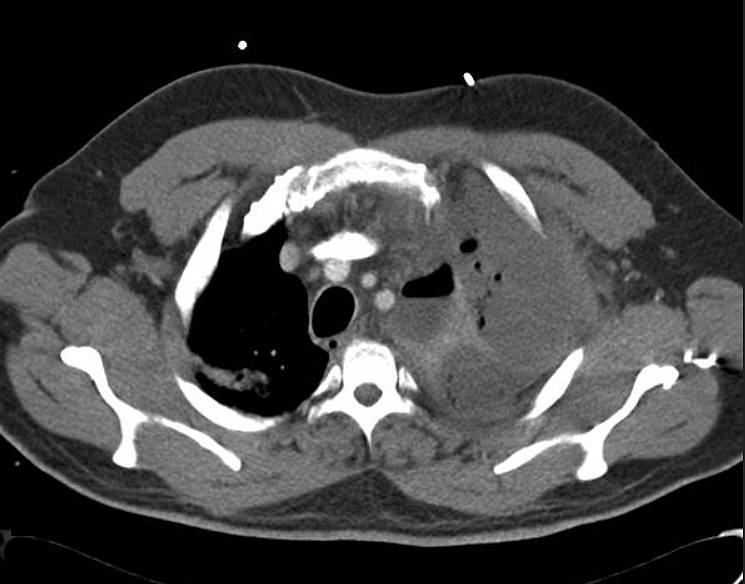

Imaging Findings

CXR revealed complete white out of left hemithorax and mediastinal shift to opposite side raising the possibility of massive pleural effusion or empyema. CT thorax revealed left pyopneumothorax.